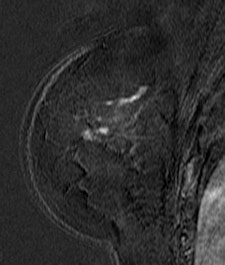

| Patient with breast cancer (invasive ductal carcinoma, grade II). MR-subtracted images (three minutes after contrast medium injection) before (left) and at the end (right) of the neoadjuvant chemotherapy. Initial staging: unifocal infiltrating cancer. After treatment, even if there is a decrease in size of the cancer, its long axis (RECIST) is unchanged with a multifocal shrinkage of the tumor. Unsuccessful first breast-conserving surgery, then mastectomy. Image courtesy of Dr. Anne Tardivon. |